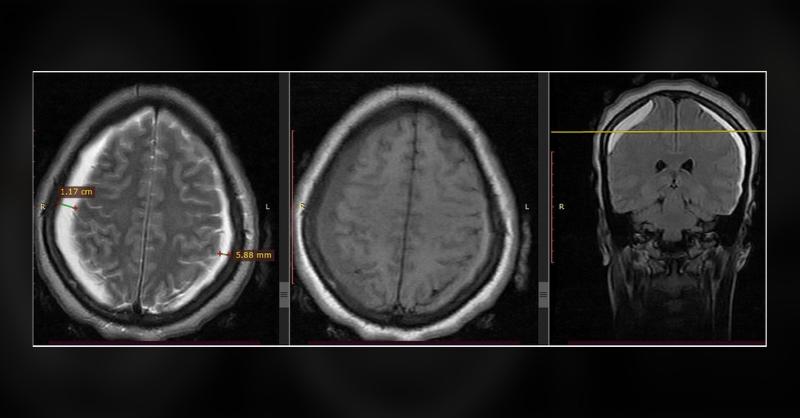

A 25-year-old woman presented with complaints of severe, global headaches and double vision, which had persisted for four weeks following a cesarean section. The cesarean was performed using spinal anesthesia due to poor progress during labor. Despite receiving multimodal analgesia, her headache showed no improvement. Neurological assessments revea

Management of Chronic Bilateral Subdural Hematoma and Bilateral Abducens Nerve Palsy Post-Spinal Anesthesia